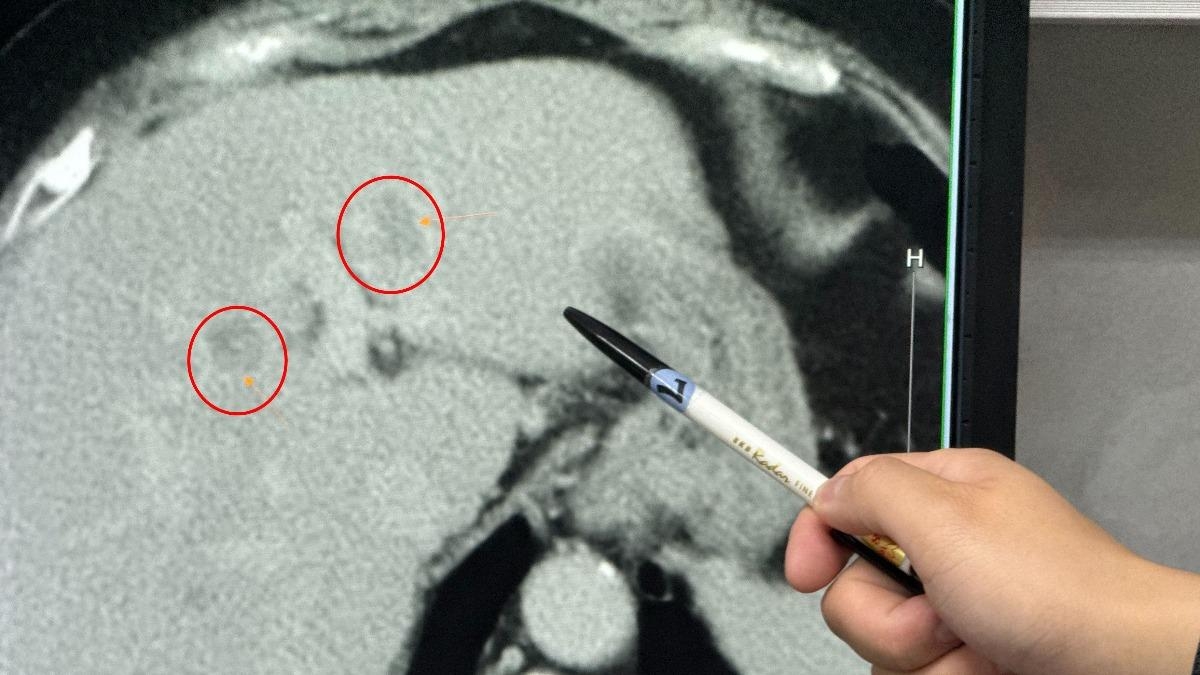

【肝臟/健康/肝炎/喝酒/重度脂肪肝/肝癌/食物】據台媒《TVBS》報道,台灣大甲李綜合醫院駐診外科醫生吳坤達分享,台中有一名60多歲的婦人非乙、丙型肝炎病毒帶原者,亦沒有喝酒嗜好,惟她到腸胃科照超聲波時,卻發現有重度脂肪肝和疑似腫瘤,進一步檢查確認,其肝臟的左外側葉及左葉中部各有1個腫瘤。

台中一名60多歲的婦人,太愛吃甜食、水果,導致重度脂肪肝進而罹患肝癌。(圖/大甲李綜合醫院提供)

吳坤達在手術期間,發現該婦人脂肪肝佔肝臟的40%至60%以上。術後該婦人表示平日沒有運動習慣,且很喜歡吃甜食、蛋糕,吳坤達在查房時,也常看到她旁邊有甜點、水果,估計她平日吃下過多的甜點,導致脂肪肝產生。